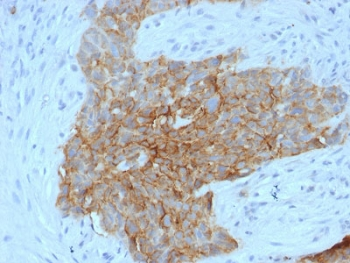

IHC staining of FFPE human ovarian carcinoma tissue with SLC2A1 antibody (clone GLUT1/7308). Inset: PBS used in place of primary Ab (secondary Ab negative control). HIER: boil tissue sections in pH9 10 mM Tris with 1 mM EDTA for 20 min and allow to cool before testing.